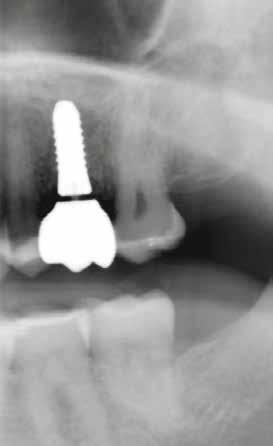

lási csavarokat (PEEK titáncsavarral) maximum 15 Ncm-rel húztuk meg (3–6. ábra). Az összes implantátum kiváló stabilitást mutatott (a mérésekhez Periotestet használtunk, a Medizintechnik Gulden jóvoltából), és teljesen osszeointegrálódott. Ezt a radiológiai vizsgálatok is megerősítették.

3. a–b ábra: Röntgenfelvételek három hónap után (a) és a gyógyulási csavarok behelyezve (b, 1. eset).

4. a–b ábra: Röntgenfelvételek öt hónappal később (a) és a gyógyulási csavarok behelyezve (b, 2. eset).

5. a–c ábra: Röntgenfelvételek öt hónappal később (a) és a gyógyulási csavarok behelyezve (b és c, 3. eset).

6. a–b ábra: Röntgenfelvételek öt hónappal később (a) és a gyógyulási csavarok behelyezve (b, 4. eset).